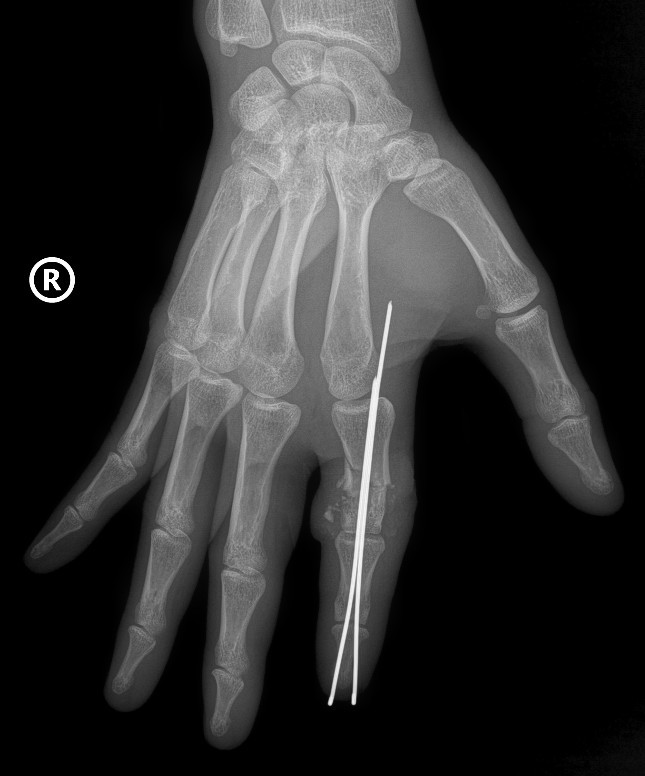

Två kirurgiska team sattes in parallellt, ett team rengjorde och förberedde det avhuggna fingret, det andra teamet förberedde stumpen. Fingerbenet positionerades och fixerades med en specialnål för att skapa en stabil axel, sen- och ligamentsystemet återställdes.

I synnerhet restaureras nerver och små blodkärl på endast cirka 0,8–1 mm med hög precision under ett kirurgiskt mikroskop med specialverktyg för att säkerställa återställning av blodcirkulationen till den avskurna delen.